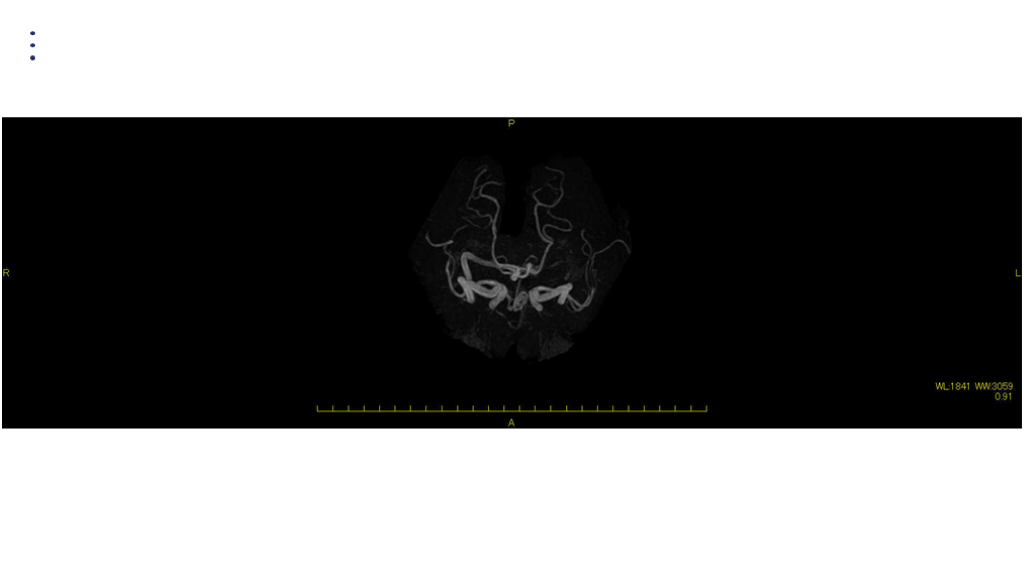

画像 所見 DAY 14 MRA 悪化